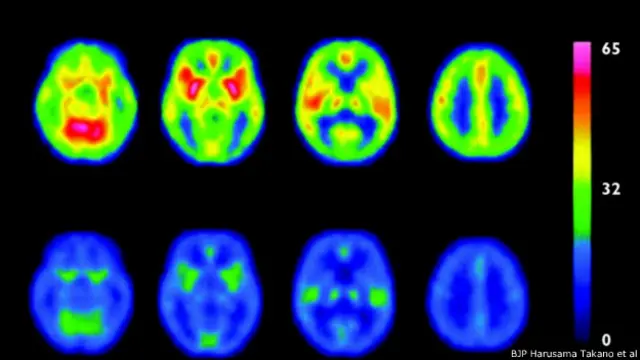

Fuente de la imagen, BJP Harusama Takano et al